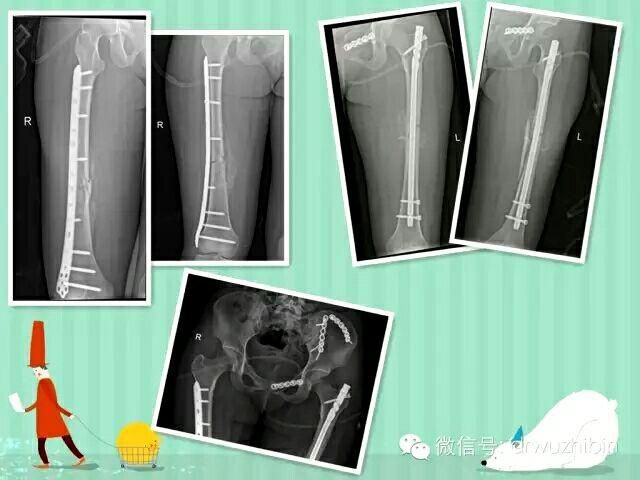

• 多發性創傷  永遠的挑戰 多發性創傷 永遠的挑戰2016-03-07

随着車禍、高處墜傷、地質災害等事件的逐步增多,多發性創傷、多發性骨折的患者也逐漸增多,此類病人損傷嚴重,緻死率、緻殘率比較高,對任何骨科團隊都是一個很大的挑戰。

康美醫院充分發揮整個外科團隊的協調作用,按照保命-保肢-保關節-保功能的治療原則,準确評估病情,制定合理治[ 查看詳細 ]